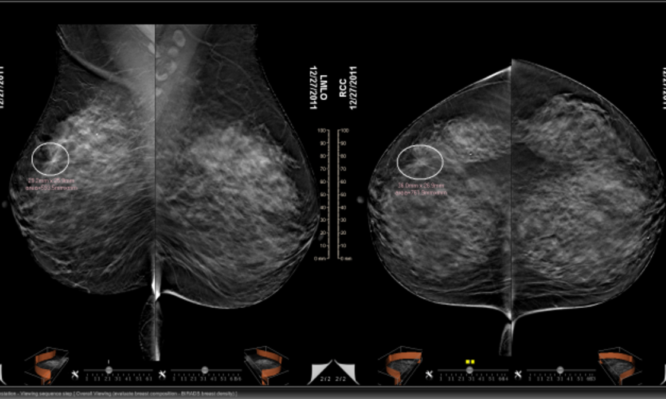

Με την τεχνολογία της τομοσύνθεσης, (Digital Breast Tomosynthesis) ο μαστός απεικονίζεται με πολλαπλές λεπτές τομές του ενός χιλιοστού, στοιχείο που δεν επιτρέπει σε τίποτα να διαφύγει του ελέγχου. «Με αυτόν τον τρόπο», τονίζει ο κ. Μαλακάσης, «η μαστογραφία αποδεικνύεται η πιο αξιόπιστη εξέταση για τη γυναίκα, ακόμα και στις περιπτώσεις πολύ πυκνών μαστών, οι οποίοι ‘’ευθύνονται’’ για το συχνό φαινόμενο της ψευδούς αρνητικής διάγνωσης σε πρώιμο στάδιο».

Υπενθυμίζεται ότι η τομοσύνθεση, είναι μία καινούργια τρισδιάστατη (3D) τεχνολογία απεικόνισης μαστού, με υψηλότερη διαγνωστική ακρίβεια στη διάγνωση των παθήσεων του μαστού, έναντι της κλασικής μαστογραφίας, καθώς έχει τη δυνατότητα να ξεχωρίζει τα ύποπτα ευρήματα, τα οποία οδηγούν στην ανεύρεση και της πλέον μικρής βλάβης.